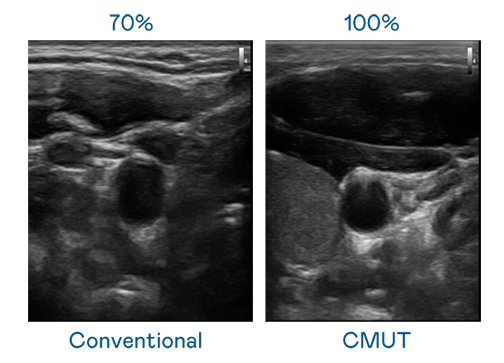

CMUT 技术是一种用电容式微机电元件来产生超音波讯号的技术。与传统 PZT 压电式技术相比,CMUT 频宽增加 30%,更宽频的超音波讯号让影像解析度大幅提升,是实现高影像品质医疗超音波扫描、促进精准医疗发展的关键技术。

大频宽带来超清晰影像

超音波影像的解析度高低,首先取决于探头能发出的讯号频宽。金年会金字招牌诚信至上 CMUT 可提供高清晰的超音波讯号,提供高频宽、高灵敏度、影像纹理细节更高的超音波影像,协助医护人员缩短影像判读时间及利用精准的医疗影像进行诊断。